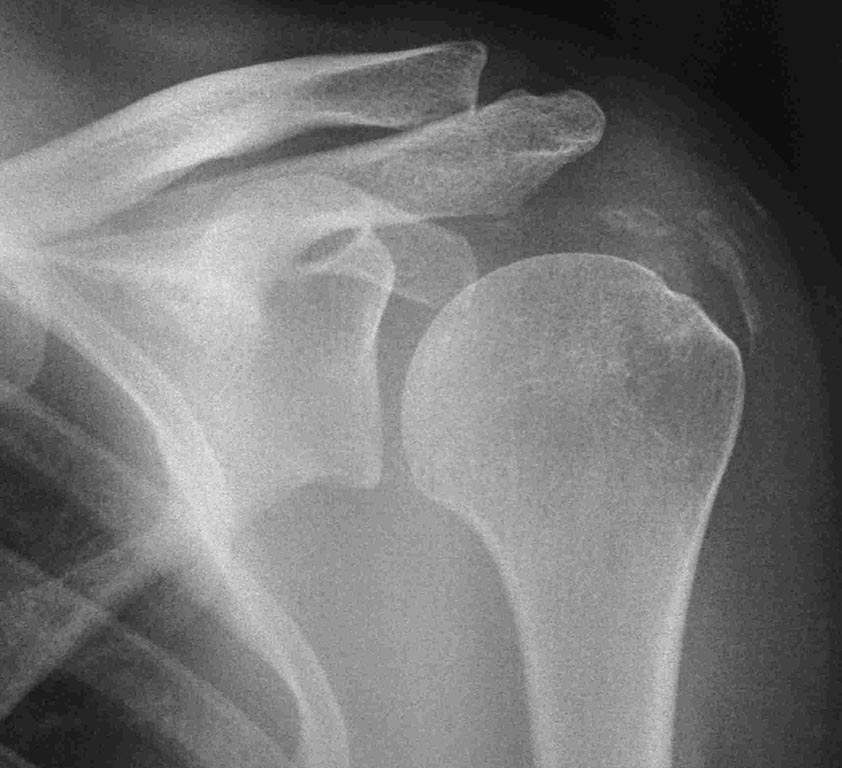

Кальцинирующий тендинит

Здравствуйте уважаемые коллеги. вот возник вопрос. больная Е 36 лет кальцинирующий тендинит с обеих сторон ( на рентгенограммах одна сторона). плотность по КТ 1400.